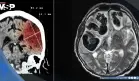

Uno de los temas más llamativos de su ponencia fue la descripción de la neuralgia del trigémino, una condición extremadamente dolorosa que puede estar relacionada con la esclerosis múltiple y que afecta los nervios de la cara.

"Se ha llegado a conocer como la ´enfermedad del suicidio´ por la intensidad del dolor que provoca. Es un dolor eléctrico, súbito, que puede repetirse varias veces al día. Hay pacientes que pasan años sin diagnóstico correcto o sin acceso a un tratamiento efectivo", explicó.

Para estos casos, el Dr. Ibarra mencionó el procedimiento de bloqueo del ganglio de Gasser con radiofrecuencia, una técnica avanzada de intervención neurológica que, según sus estadísticas, tiene una efectividad de entre 95 y 98% en el alivio del dolor.